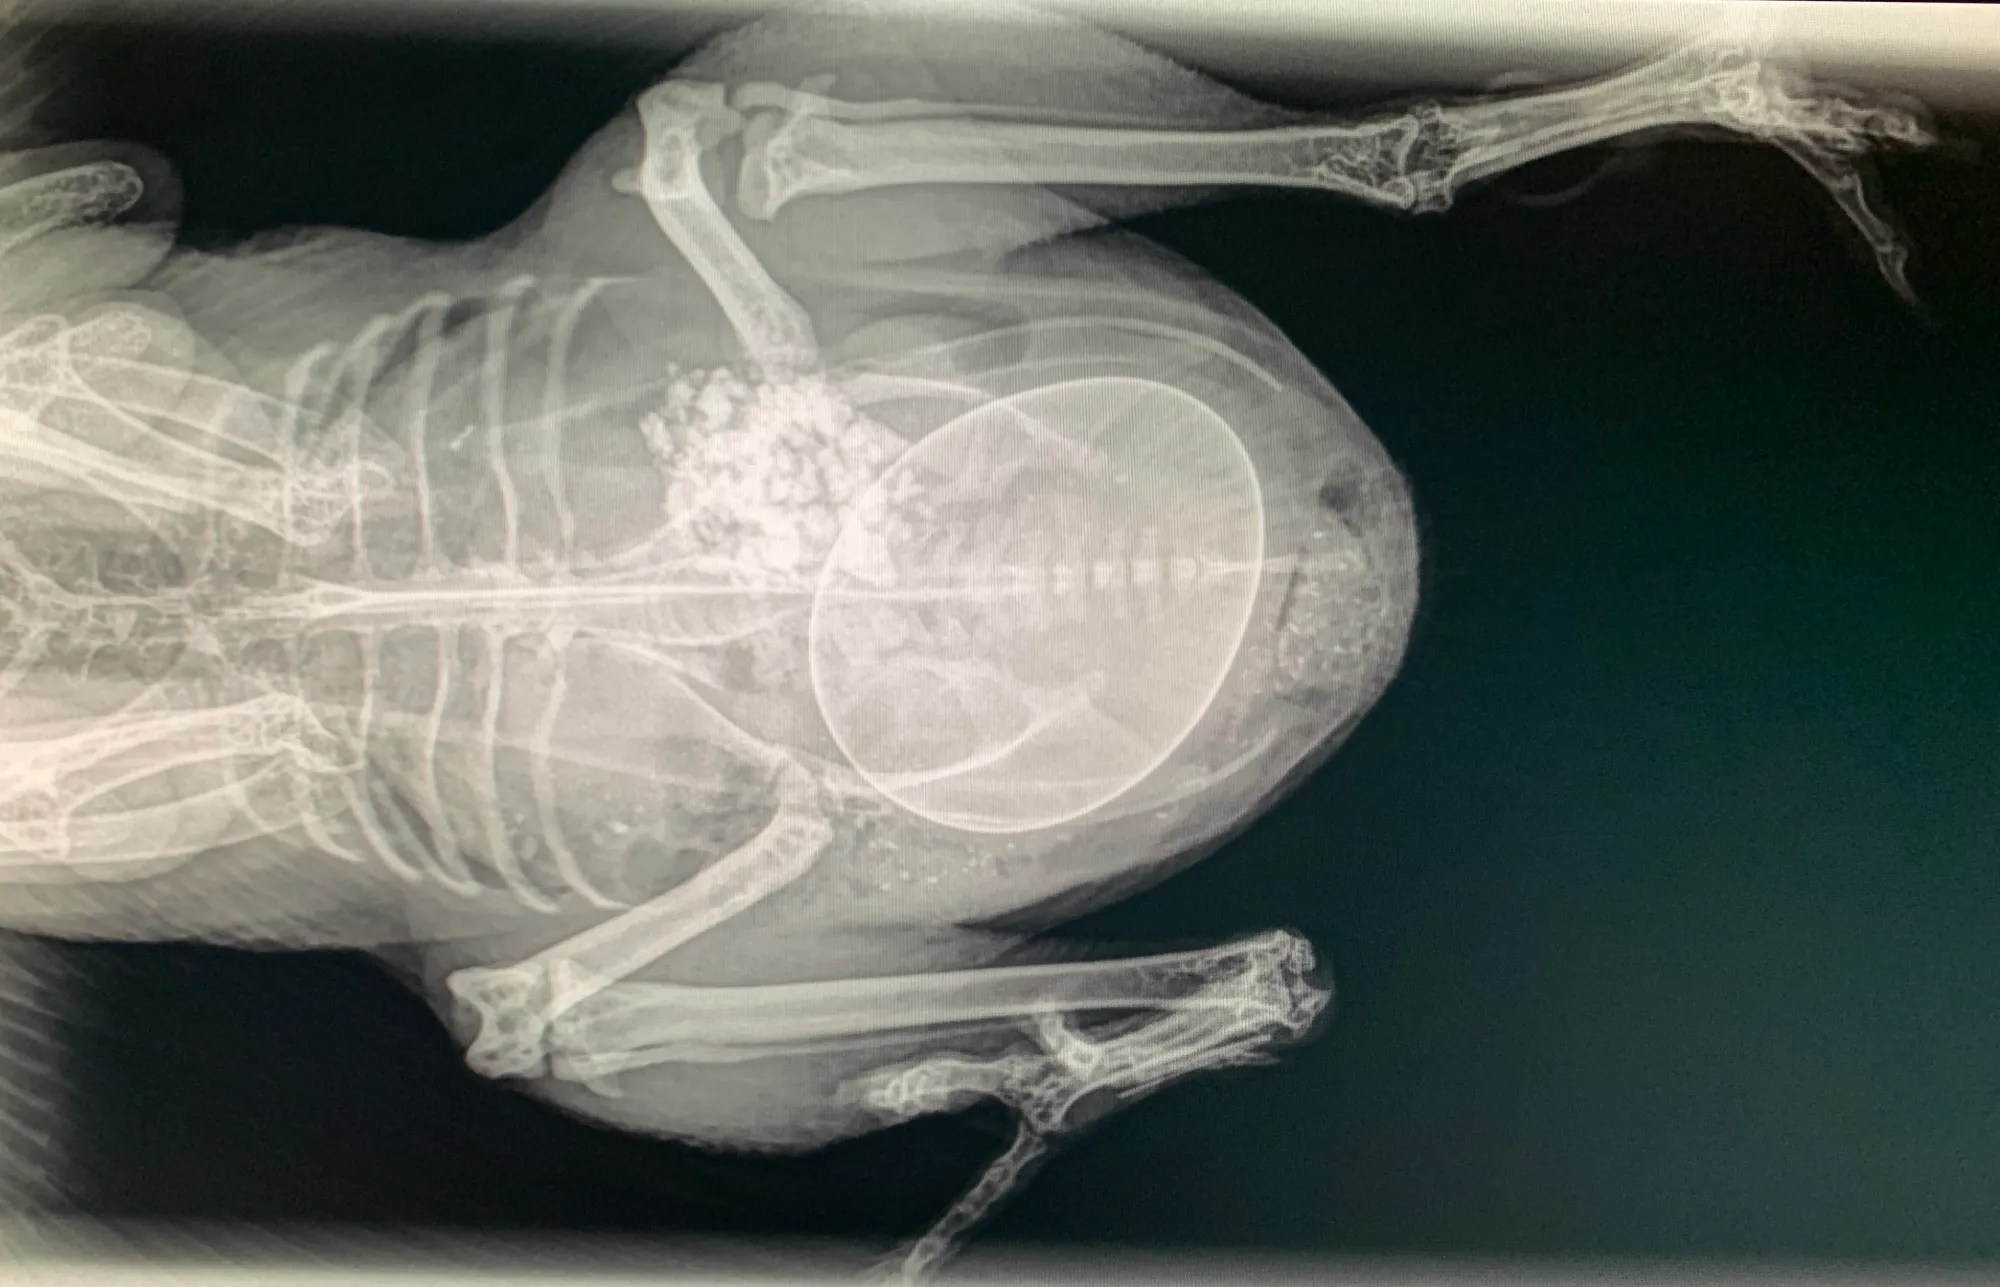

Egg Binding

Egg binding occurs when an egg gets stuck in the reproductive tract causing the hen difficulty in laying it. The recommended treatment is to support the hen in whatever ways possible to lay the egg: a hot Epsom salt bath to relax the muscles and calcium (crushed Tums in water) to help with the contractions. Inserting lube into the vent can also help ease the egg out.

If it becomes necessary, like in the case of one of my hens, you may have to break the egg and carefully extract all the contents. The risk is that any yolk remnants left in the reproductive tract can become the perfect medium for a bacterial infection like egg yolk peritonitis.

Egg binding usually occurs in young layers or when attempting to lay very large eggs. Other causes include: calcium deficiency, obesity, oviduct infections or the use of supplemental light to force laying year round. I’m careful to give my birds a good supply of oyster shells, crushed eggshells and a healthy balanced diet. I don’t use supplemental lighting in winter, which allows them a much needed break from laying.